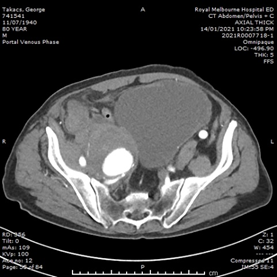

He had normal inflammatory markers, Hb 133g/L and Creatinine 104umol/L. A Computed Tomography (CT) scan of the abdomen and pelvis was performed, with the differentials considered being incarcerated inguinal hernia, diverticulitis or malignancy. However, the CT showed a 75mm, contained ruptured right internal iliac artery (IIA) aneurysm, with no active contrast extravasation (Figure 1). There was perianeurysmal haemorrhage in the right iliac fossa which extended into a small fat-containing inguinal hernia (Figure 2). There was also bladder distension and moderate-to-severe right hydroureteronephrosis secondary to the large aneurysm.

Figure 2 CT images of the abdomen and pelvis. (A) Coronal image showing perianeurysmal haemorrhage in the right iliac fossa extending into an inguinal hernia. (B) Axial image showing the right inguinal hernia containing blood, as compared to left inguinal hernia containing fat only.